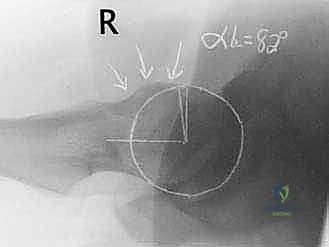

- الأشعة السينية (X-rays): لتقييم شكل العظام، قياس "زاوية ألفا" (Alpha Angle)، وتحديد وجود نتوءات الكامة أو الكماشة.

يحدث هذا النوع عندما لا يكون رأس عظم الفخذ كروياً بشكل مثالي. بدلاً من ذلك، تتكون نتوءات عظمية إضافية عند منطقة التقاء رأس وعنق الفخذ. هذا الشكل غير الدائري يجعله يحتك بقوة بحافة التجويف (الحُق) أثناء الحركة، مما يؤدي إلى "كشط" وتمزيق الغضروف والشفا الحقي. هذا النوع شائع جداً بين الشباب والرياضيين الذكور.

* إذا كان الانحشار من نوع "الكامة"، يتم نحت عنق عظم الفخذ ليعود لشكله الانسيابي.